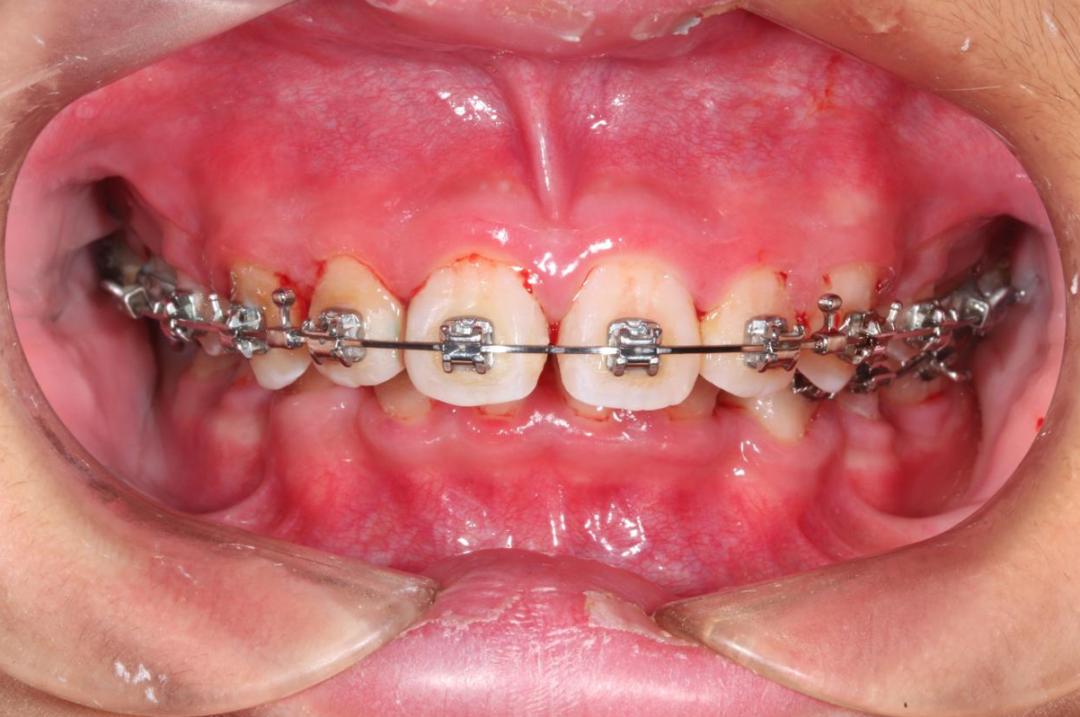

炎症状态下的牙龈充血脆弱,啃苹果、吃坚果、刷牙以及正畸治疗时的牙龈受到机械刺激,都会出血。

正畸刺激引起的牙龈出血